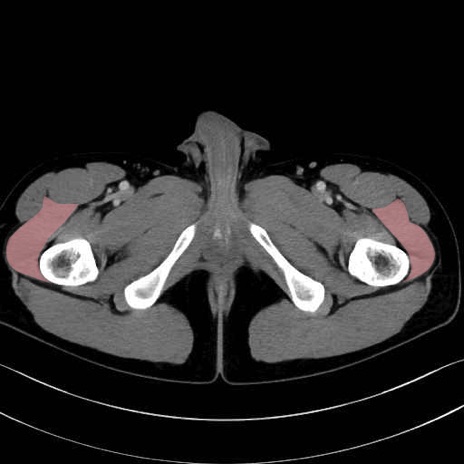

外側広筋 (Vastus lateralis)